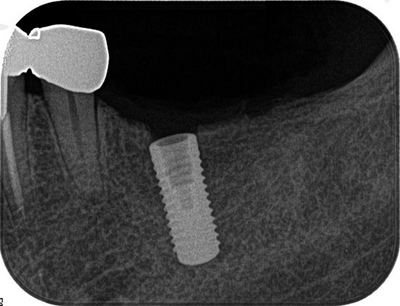

オペ終了後のレントゲン写真です。

6週間後には負荷をかけることが可能になります。